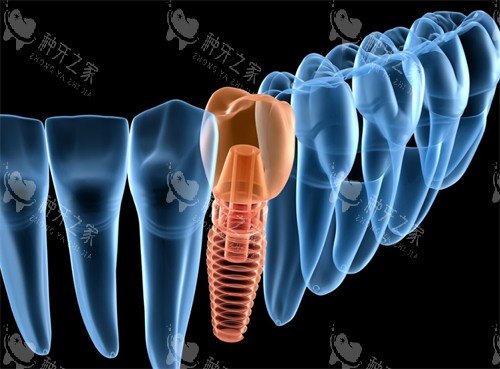

3. 种植牙类:集采降价后,种牙不再是“奢望品”

单颗种植:国产种植体3000元起,韩国登腾种植体4500元起,瑞士ITI种植体1.2万元起。

集采后价格直降50%,部分医院推出“种植+牙冠”套餐。

半口/全口种植:All-on-4半口种植4万元起,All-on-6半口种植5万元起;全口即拔即种6万元起,一站式解决无牙问题。